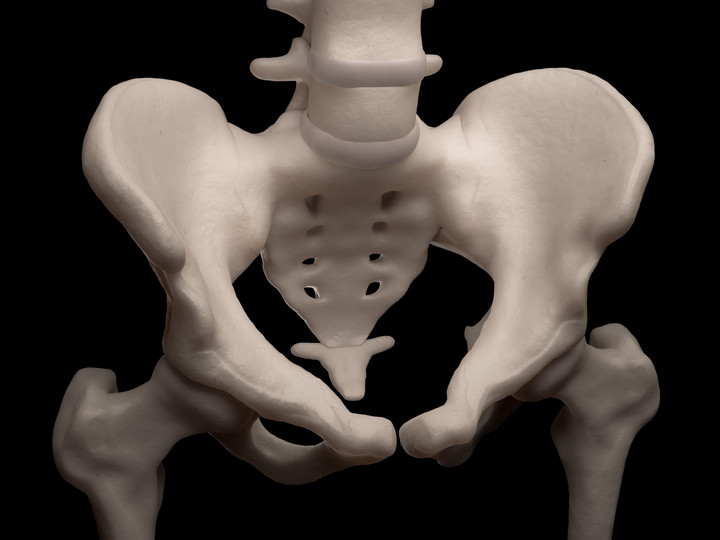

Kość ogonowa – inaczej kość guziczna. Jest to końcowy odcinek kręgosłupa u człowieka, który złożony jest z trzech do pięciu zrośniętych ze sobą kręgów. Największy z.

Kość ogonowa zwana jest też kością guziczną. Nie bierze udziału w dźwiganiu ciężaru tułowia. Nie pełni ona w organizmie żadnej funkcji, a jej uraz może być.

Kość ogonowa - urazy a ciąża. 1. Kość ogonowa - anatomia. Kość ogonowa (inaczej określana jako kość guziczna) to końcowy odcinek kręgosłupa. Jest.

U człowieka kość ogonowa nie spełnia funkcji dźwigania ciężaru ciała, ale tak jak inne elementy kręgosłupa jest podatna na wszelkiego rodzaju urazy. Ból w.

Kość ogonowa − po co ona człowiekowi? Kość ogonowa usytuowana jest w końcowym odcinku kręgosłupa. Nazywana jest zarówno kością ogonową (ze względu na to, że u.